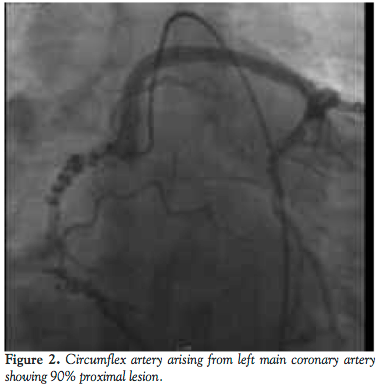

He was admitted for elective cardiac catheterization. Cineangiographic evaluation revealed a single vessel coronary artery arising from the right coronary cusp supplying the entire left system and also the right coronary artery. The right coronary artery was abnormal with significant tortuosity in the proximal and mid segments more consistent with varicose anatomy. Distally the RCA was normal. It gave rise to a posterior descending artery, which had an ostial 60% stenosis. The posterior lateral branch was a small caliber vessel and was normal. The left anterior descending artery (LAD) was a moderate caliber vessel and had no obstructive disease. The first diagonal branch divided into bifurcating branches of which the lower branch had a 70% stenosis. The circumflex artery was a very large caliber vessel that had a proximal 90%-95% stenosis. Left to right collaterals were noted.

CT angiography showed that coronary artery calcium score was 966. All vessels originated in the common origin at the right coronary cusp. The left main was long and normal as it coursed anteriorly to the pulmonary artery before bifurcating. The LAD had diffuse scattered calcifications in the proximal portion, but no critical lesions. The circumflex had diffuse severe calcifications proximally. There was a proximal 90% stenosis, which was mixed plaque. The RCA was dominant. The midportion of the vessel had a corkscrew configuration. Proximal to this was 50% stenosis of soft plaque.